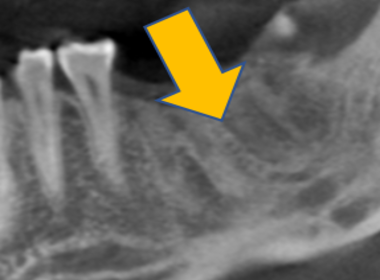

| 0114 #16 右上第一大臼齒 |

![]() |